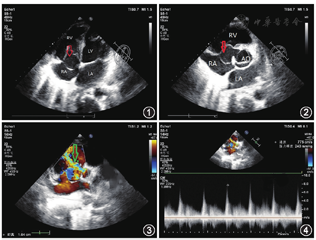

例2患者,女,34岁,因"活动后心慌、气促1个月,体检发现先天性心脏病2周余"入院。体格检查:胸骨左缘3~4肋间闻及连续响亮的杂音。外院经胸超声心动图显示:室间隔于膜部可见回声中断,形成大小约18 mm×12 mm的瘤样病变,向右心室突出。彩色多普勒超声:可见异常的穿隔血流宽约10 mm,收缩期从左心室经室间隔膜部缺损口进入右心室,血流束以红色为主,多彩镶嵌;连续多普勒:取样容积置于缺损口可见收缩期正向高速湍流频谱,左向右分流速度约4.63 m/s,压差86 mmHg。诊断提示:室间隔膜部缺损伴膜部瘤形成。我院经胸超声心动图显示:无冠窦可见一大小约13.8 mm×10 mm的囊袋状结构凸起,在三尖瓣隔瓣上方突向右心房侧,破口宽约6 mm,可探及双期血流频谱,VP 4.8 m/s。诊断提示:无冠窦瘤破入右心房(图5,图6,图7,图8)。术中经食道超声心动图示:主动脉窦瘤破入右心房,无冠窦可见一大小约7 mm×14 mm的囊袋状结构凸起,在三尖瓣隔瓣下方突向右房侧,破口宽约6 mm,可探及双期血流频谱,VP 5.04 m/s,PG 102 mmHg。术中见三尖瓣隔瓣上方见一大小约14 mm×10 mm囊袋状突出,剪开囊状袋,见基底部约6 mm的缺损,修补缺损窦部。患者术后恢复良好,顺利出院。

误诊分析:(1)二维超声:外院超声心动图可见室间隔膜部回声中断,形成囊袋样结构,并未诊断出突出结构为主动脉窦部,可能系未正确认识少见病的诊断要点;(2)彩色多普勒:外院超声心动图仅提示可探及一束左向右的异常血流信号,并未明确分辨出此束血流信号来源于囊袋样结构破口处;(3)频谱多普勒:外院超声心动图仅提示异常血流信号收缩期流速,并未诊断为双期血流频谱。